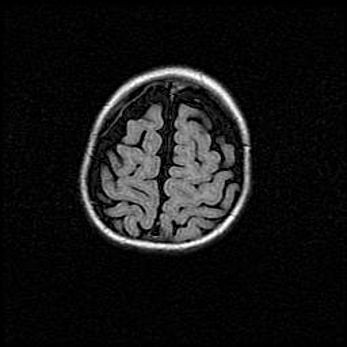

Неполная лизэнцефалия (пахигирия). Открытая гидроцефалия.

Возраст: 17 дней

Вес: 3110 г

Пол: мужской

Окружность головы: 33,5 см

Срок гестации: 35-36 недель

Лизэнцефалия—недоразвитие корковой пластинки и мозговых извилин в результате нарушения миграции нейронов коры. Поверхность мозговых полушарий гладкая. Микроскопически выявляется отсутствие нормальных слоев коры и скопление групп нейронов в подкорковом белом веществе.

Пахигирия—уменьшение числа вторичных извилин. В пораженном полушарии нервные клетки образуют толстый недифференцированный слой с неправильно расположенными нервными волокнами и группами гетеротопных клеток. Нервные клетки незрелые. Белое вещество истончено. При этом нередко аномально развит корково-спинномозговой путь.